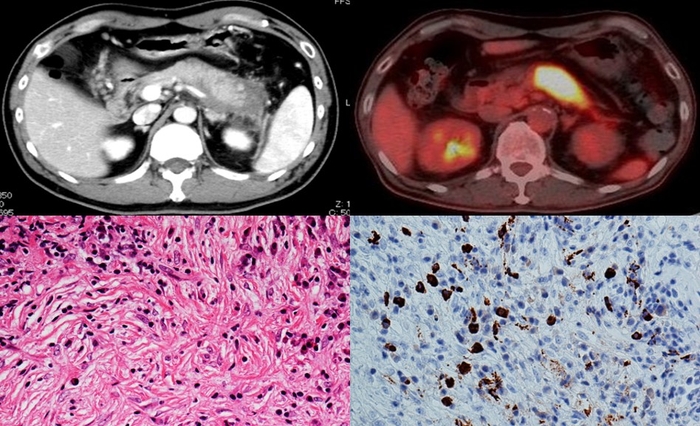

研究グループは、腸管バリアの破綻、腸内細菌バランスの乱れと自己免疫性の関係について調査しました。MRL/MpJマウスという自己免疫疾患モデルのマウスを用いて、ウイルスのRNAに類似した分子であるpoly(I:C)を注射し、自己免疫性膵炎を誘導しました。同時に高分子デキストランを飲水させることで、腸管バリア機能を障害しました。その結果、腸管バリアの破綻が自己免疫性膵炎を悪化させることを明らかにしました。この激しい膵炎を起こしたマウスでは、膵臓と大腸にIFN-αとIL-33を産生する形質細胞様樹状細胞が増加しており、膵臓と腸管で異常な免疫反応が共有されていました。

また、どのような菌が膵炎の悪化に関わっているのかを調べるために次世代シークエンス解析※7 を行ったところ、腸管バリアの破綻により激しい膵炎を起こしたマウスの便と膵臓からシウリ菌が検出されました。すなわち、腸内にいたシウリ菌が腸管バリアの破綻によって膵臓に移行し、膵炎悪化を起こしたと考えられます。

次に、無菌マウスとシウリ菌のみを定着させたマウスを用い、膵炎の悪化にシウリ菌が果たす役割を調査しました。無菌マウスでは少量のPoly(I:C)投与では軽度の膵炎しか起こりませんでしたが、シウリ菌のみしか存在しないマウスでは、通常では軽度の膵炎しか生じない少量のpoly(I:C)投与でも重度の膵炎を発症しました。このマウスでは、膵臓にIFN-αとIL-33を産生する形質細胞様樹状細胞を数多く認めました。このことから、シウリ菌が自己免疫性膵炎を悪化させる細菌であることが強く示唆されました。実際に、重度の膵炎を発症したマウスの膵臓から形質細胞様樹状細胞を分離して、ビフィズス菌、シウリ菌、クレブシエラ菌で刺激したところ、シウリ菌が効率よくIFN-αとIL-33の産生を誘導しました。